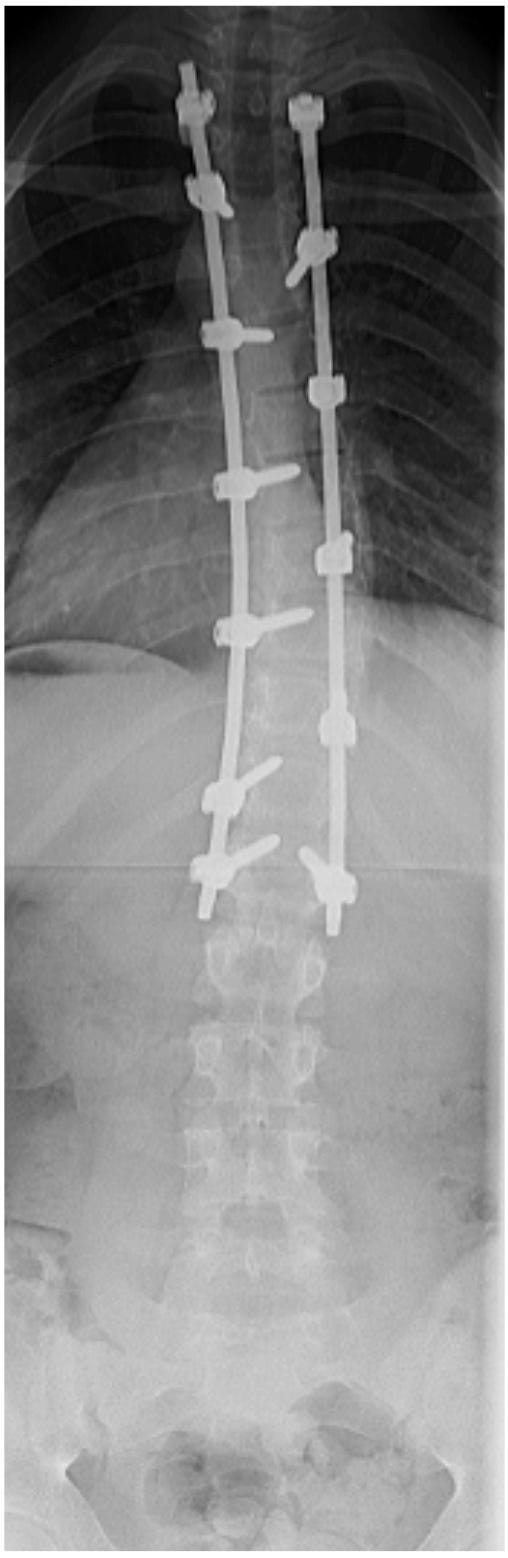

De wervelkolom wordt vastgezet met behulp van metalen staven en schroeven. Op sommige plaatsen maakt de chirurg de wervels beter passend door wat bot weg te halen. Dit zorgt ervoor dat alles stevig vast groeit.

Op de röntgenfoto’s kun je zien hoe de wervelkolom er voor en na de operatie uit ziet.

Figuur 1: scoliose voor de operatie

Figuur 2: scoliose na de operatie